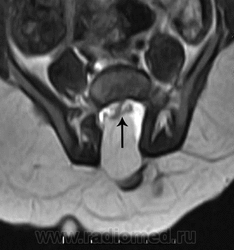

Терминальное миелоцистоцеле

Приложения:

3.cover_.giff20.medium._terminal_myelocystocele..giff21.medium._terminal_myelocystocele..giff22.medium._terminal_myelocystocele..gif